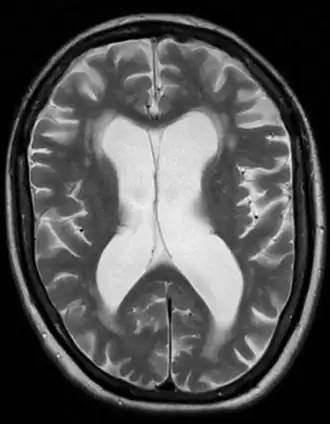

| Brain atrophy from vascular dementia | |